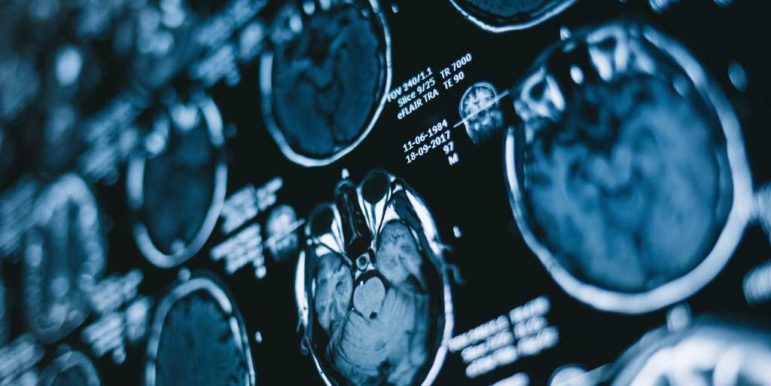

Screening, i.e. testing individuals for a disease or condition before they show symptoms, does reduce cancer deaths for certain cancers in certain populations. For example, cervical cancer screening in women age 21-65 is recommended to find and treat pre-cancerous lesions. Similarly, colon cancer screening for individuals age 50-75 can detect early-stage colorectal cancer and, in many cases, eliminate it.

But not all cancers are detectable through screening, and not all detected cancers are harmful. As Gilbert Welch, a senior researcher in the Center for Surgery and Public Health at Brigham and Women’s Hospital in Boston, explained in a 2019 piece in the New England Journal of Medicine, we are diagnosing certain cancers more, but the mortality rate for these cancers has remained the same.

For example, we are finding many more cases of thyroid cancer and melanoma now than in previous decades. New scanning technology has increased the rate of incidental findings of small harmless thyroid tumors, leading to more “findings” of thyroid cancer. Similarly, increased melanoma screening and new dermatology tools have increased diagnosis of melanoma. However, the rates of metastatic cancer incidence and mortality have remained stable since 1975, indicating that much of these new cases are overdiagnosis.

Some cancers will never grow or cause harm, but it is not always possible for pathologists to distinguish between these harmless cancers and life-threatening cancers–so we treat all cancers aggressively. The result: people are harmed unnecessarily by cascades of further testing and procedures, not to mention financial hardship.